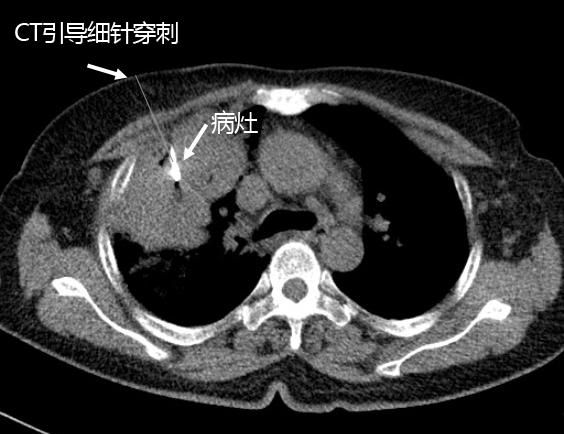

康美醫院開展經皮肺細針穿刺活檢術 ——診斷周圍型肺癌的金标準

發布時間:2018-01-22 閱讀:4137 患者劉某,女,62歲,因“發現頸部淋巴結腫大2月餘”于本月6日入院。檢查雙側頸部可扪及多個大小約1*0.5cm淋巴結,質硬,無壓痛。入院後經胸部CT增強平掃發現右肺上葉腫塊,結合腫瘤标志物檢測,考慮肺癌。

通過病理檢查結果确診爲右肺腺癌,李主任随即根據該型肺癌特點結合患者身體情況,爲其制定個性化治療方案,爲患者争取到了寶貴的治療時機,取得良好治療效果。

由于周圍型肺癌分型不同,治療方案不同。以往醫學界隻能在患者術後取腫瘤組織送病理檢查,才能确診其良惡性以及對腫瘤分型,即是先手術後确診。而經皮肺穿刺活檢術把診斷提到了前面,即先确診後治療,對周圍型肺腫瘤的診療無疑有重大意義。